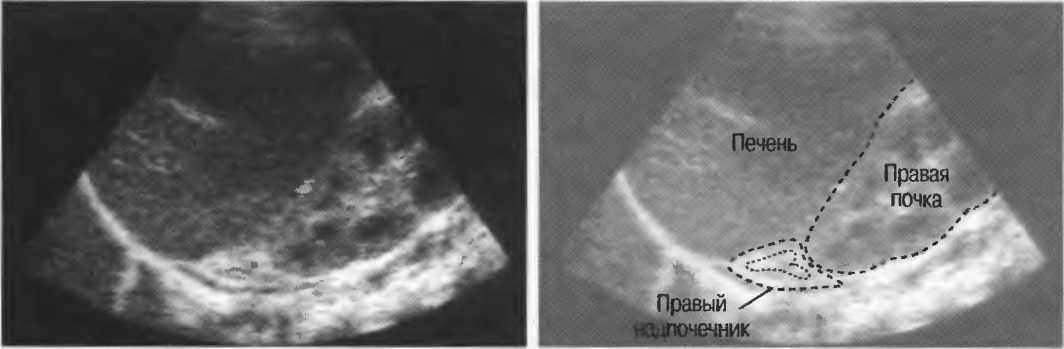

Ткань или структура, не препятствующая распространению ультразвуковых волн и таким образом являющаяся окном для визуализации более глубоко расположенных структур. Например, заполненный жидкостью мочевой пузырь создает великолепное акустическое окно, через которое происходит визуализация тазовых структур. Обычно правую почку легче визуализировать через печень, чем через толстые мышцы спины. В этом случае печень является акустическим окном. |